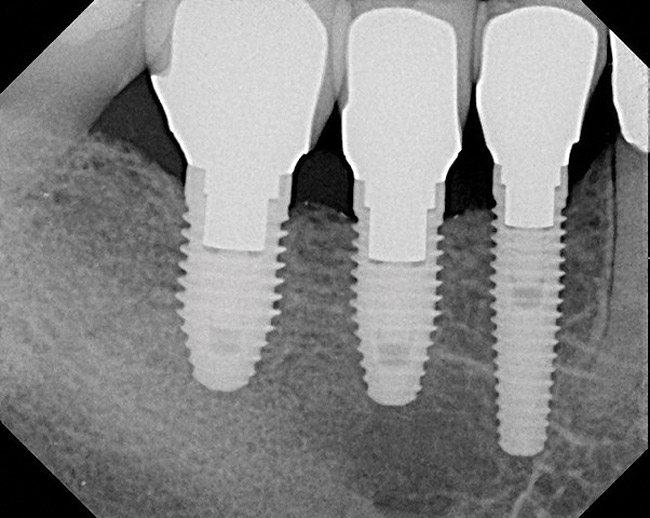

Figure 3  Periapical (PA) radiograph, definitive restoration, of patient in Figure 2.

Figure 3

Figure 2  Surgical guide with implants placed attached to implant mounts, three implants in row. Note implant spacing and varying implant diameters corresponding to individual site’s planned dental restorations.

Figure 2

When three or more implants in a row are planned, concepts of spacing and angulations, parallelism in all dimensions, proximity to anatomic structures, and relationships between implant positions and planned restorations are all significant considerations. CT/CBCT-guided surgery allows for the ideal placement of multiple dental implants according to the planned restoration while taking these issues into consideration (Figure 2 and Figure 3). Implants can be placed flaplessly and immediately loaded.6-8,11-14,25-29